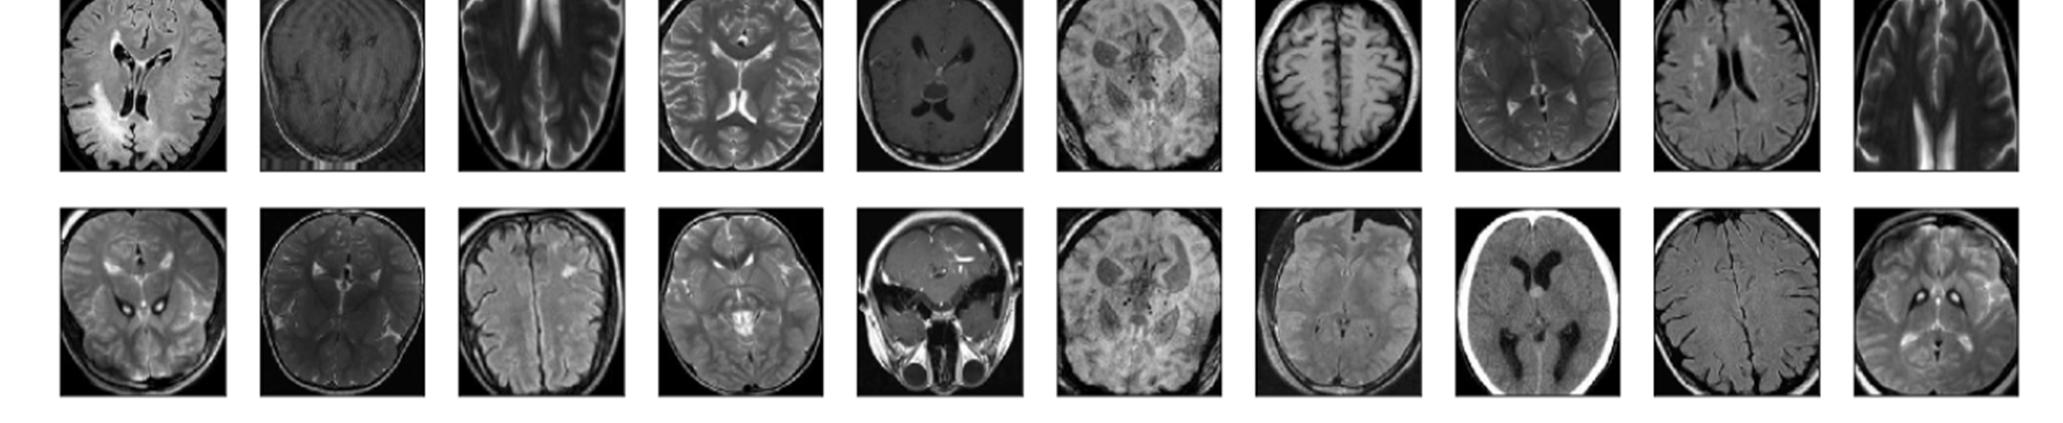

The Database was gathered from Kaggle, named ‘Brain MRI Images for brain tumor Detection’ By Navoneel Chakrabarty.[6] The dataset comprises 253 Brain MRI Images in the folders yes and no. The folder yes contains 155 timorous brain MRI images, whereas the folder no has 98 non timorous brain MRI images.

Figure1:Dataset of MRI scans containing no tumors